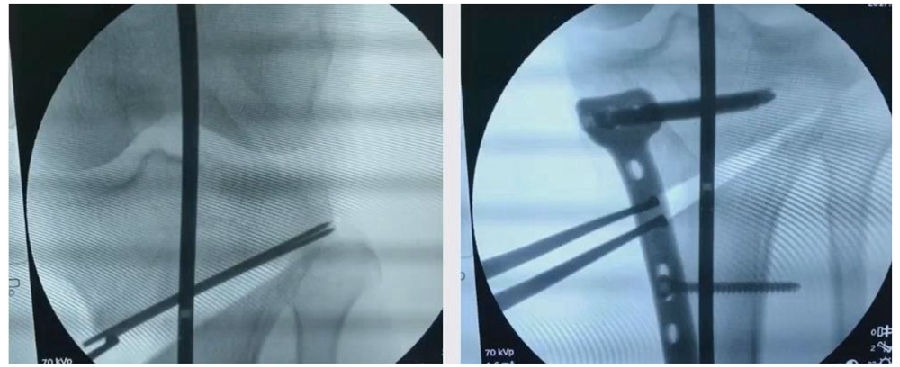

(2)Ⅱ型骨折

当出现Ⅱ型骨折时要特别注意,因为此时截骨的远端就是骨折的远端,近端只有上胫腓周围骨筋膜存在,所以相对来说Ⅱ型骨折并不稳定。

首先用拉力螺钉复位,调整好力线。然后做结构性植骨,延迟负重,所谓延迟负重就是延迟到外侧合页和上行截骨线处达到初始愈合,然后再让患者进行负重。如果不做结构植骨加延迟负重,就会出现一些非常严重的现象,如不愈合。

拉力钉复位,结构性植骨

左侧患者未植骨正常负重,术后4个月不愈合;右侧患者非结构性植骨过早负重,术后1年未愈合